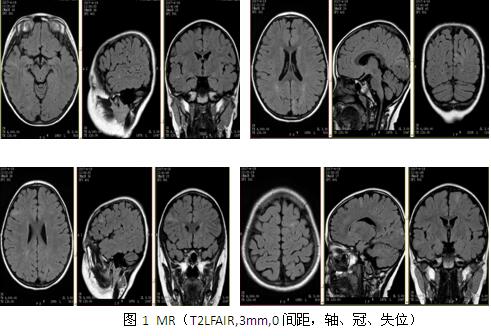

入院后检查:血常规、肝肾功能、离子、凝血、传染八项结果正常。心电图、腹部彩超、心脏彩超、胸片未见异常。韦氏全量表83,言语83,操作87,记忆86。头颅CT结果示:左侧顶枕及侧脑室周围多发钙化,左侧顶枕为著。头颅MR结果示:大脑皮层多发异常信号,考虑结节性硬化(图1)。视频脑电图示:异常脑电图Ⅲ(清醒/睡眠),间歇期:癫痫样放电,弥漫性,双后头部著;发作期:临床:强直(轴-肢带型),EEG:发作型,弥漫性,双后头部著。PET:左侧枕叶内侧面代谢明显减低(图2)。入院诊断:

讨论:患者发作间歇期及发作期均为双侧弥漫性放电,但后头部明显,考虑局灶性癫痫,患者颅内多发病灶,考虑症状性局灶性癫痫,患儿有皮肤色素脱失斑,影像学有脑皮层发育不良,符合2012年结节性硬化专家共识的结节性硬化诊断标准。患者多种抗癫痫药物无效,考虑外科手术治疗,有研究表明:钙化结节和最大结节很有可能是结节性硬化患者的致痫结节,手术切除能取得良好手术效果,儿童脑发育不完善,局灶性癫痫往往以全部性发作为表现形式,患者发作形式为强直发作,是以全部性发作为表现的局灶性癫痫,结合VEEG、PET-CT最终予左枕内侧面结节切除,术后取得良好的效果,相关文献研究显示:儿童后头部癫痫的症状学,显示了重要的年龄相关性,与成人相比,儿童发作时间更短但更频繁,很少有先兆或视觉感觉症状,偶发复杂运动及全身强直阵挛,而发作微笑,点头和行为改变是典型的特征,强直发作的患者中(SPECT)检查结果在额叶辅助运动区(SMA)的高灌注,考虑后头部癫痫向前传导至SMA可能,还需进一步证实。